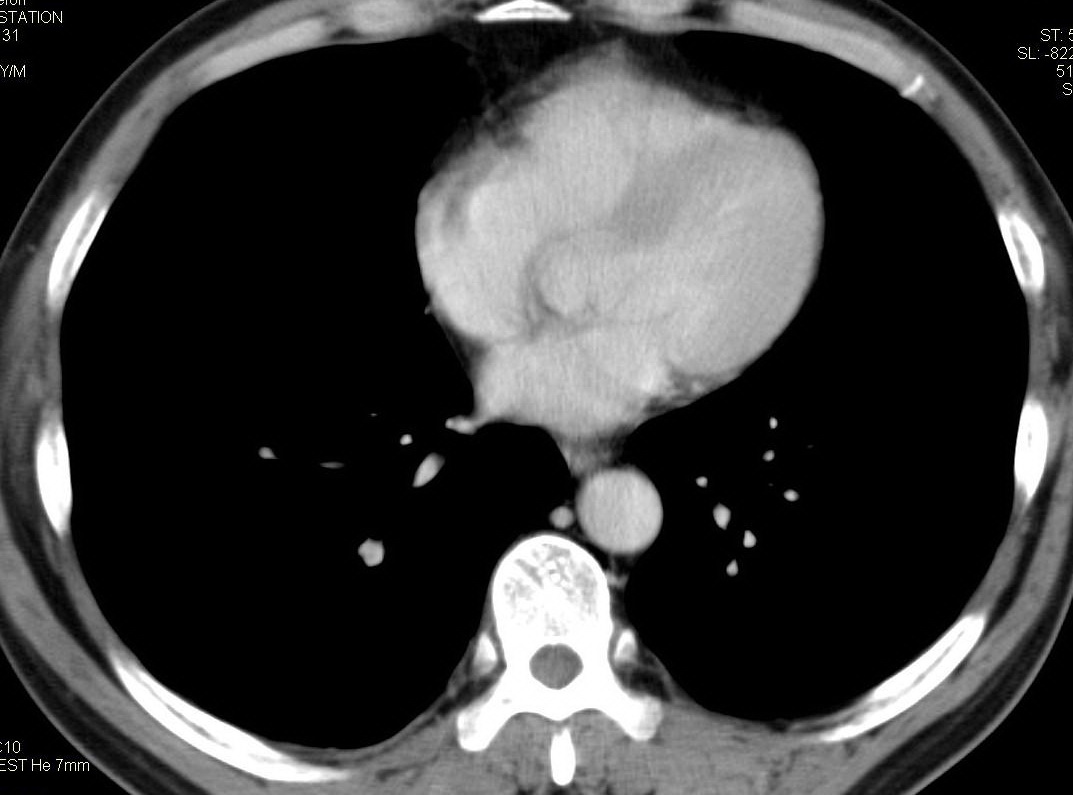

标题: CT15857:男性 58岁 咳痰带血 无发热 请各位大侠发表一下意见 [打印本页]

标题: CT15857:男性 58岁 咳痰带血 无发热 请各位大侠发表一下意见

两肺下叶肺纹理增多、增粗并呈“树芽状”改变。支气管扩张呈囊状,部分呈柱状改变。其周围可见散在的斑片样及条索样密度增高影,右肺下叶近叶间胸膜可见一形态不规则的高密度结节影,并与胸膜粘连。

考虑:支扩并发感染。

双肺多发炎性病灶,结核可能性大,建议抗炎治疗复查.右肺下叶前基底段结节灶,高度警惕肺癌可能

双肺间质性改变(间质纤维化?)伴支扩。右肺下叶有毛刺的小结节,考虑周围型肺癌可能性。